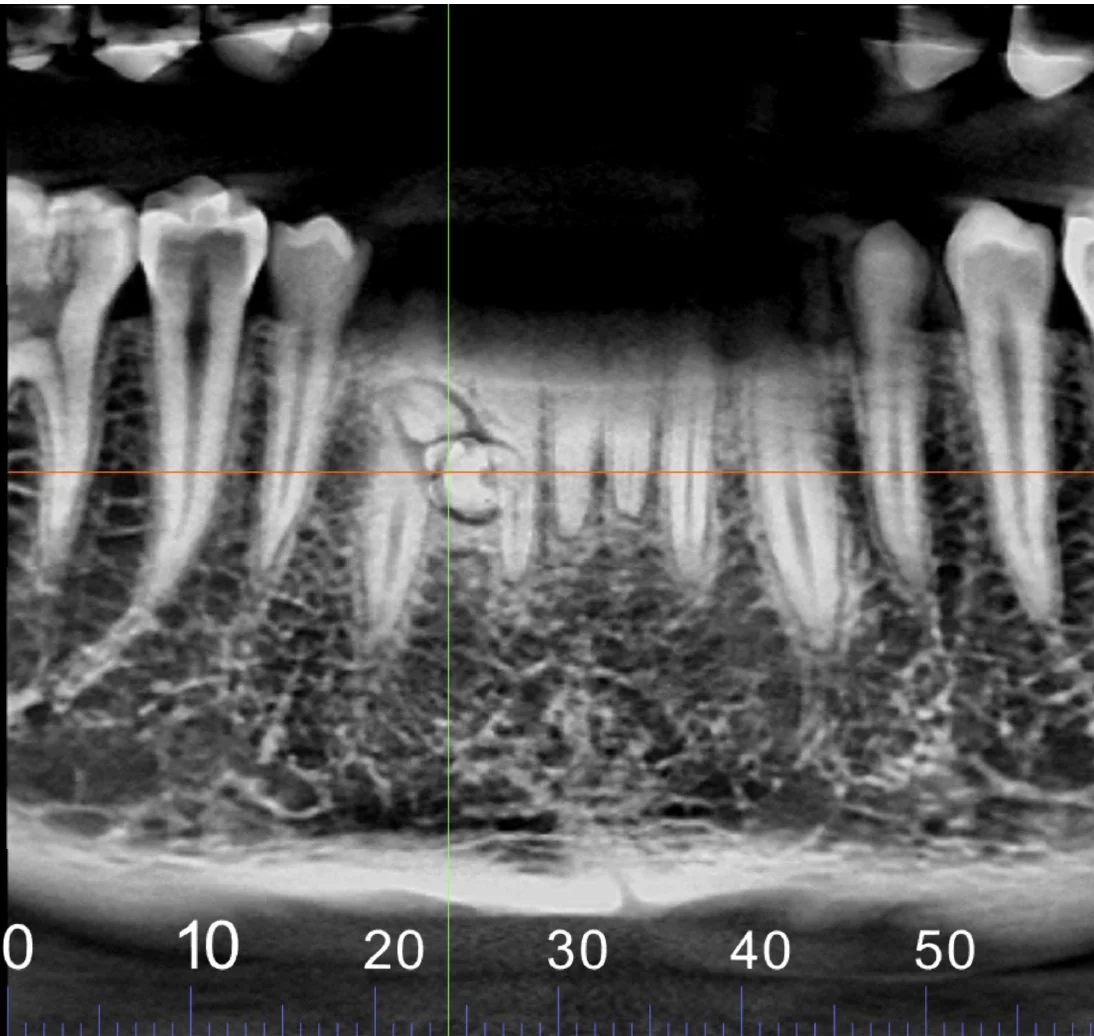

• An image portfolio report translates the 3D volume into clear and organized image sets enabling patient communication in a way they will understand. Images are correctly oriented and have true size and scaling for optimum planning.

Image portfolio reports are fully customizable to give you the information you need to prepare and communicate your treatment plan.